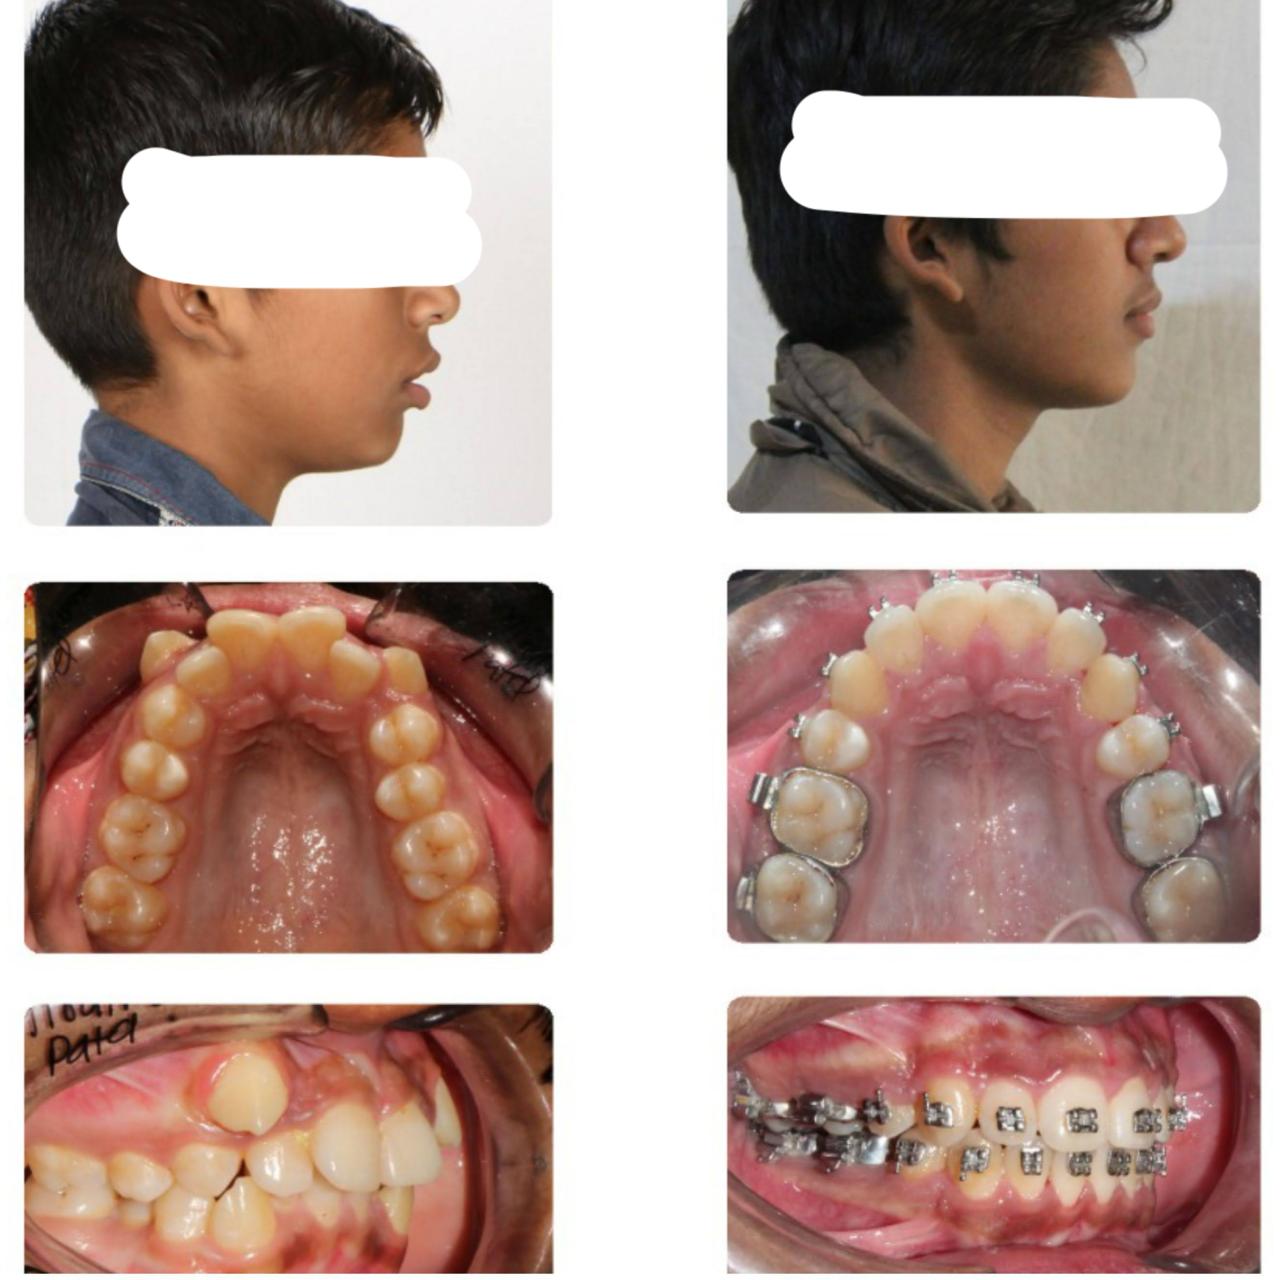

Patient's Gallery

Clinical case photos — click any case to open a larger view with title and description.